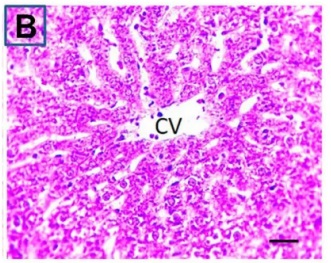

Put the liver tissue section under a microscope, and you can see that cisplatin can cause liver congestion (the blood that should return to the heart is blocked and stagnates in the hepatic veins), cell degeneration (vacuoles appear, which is the earliest change in cellular injury), apoptosis and necrosis, but these conditions can also be alleviated by using Ganoderma lucidum.

Figure 2 Effects of cisplatin and Ganoderma lucidum on hepatocytes